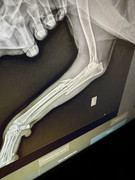

Пес из этого поста https://www.facebook.com/groups....6848815                Даже не знаем, что тут написать.. старый никому не нужный травмированный пес, сегодня его нашли возле момо, был дезориентирован, не мог встать. Животные-старички — наша боль. Невозможно смотреть на их страдания и не попытаться сделать хоть что-то. Отвезли в клинику. Перелом челюсти, оскольчатый перелом лапы, в ушах мрак.. такой жести мы не видели еще, гной вперемешку с кровью, одно ухо фактически гниет заживо. Теперь его зовут дедушка Ваня. Под сильными обезболами он остается в стационаре стабилизироваться и завтра будет операция (лапа и челюсть). Просим помощи! В первую очередь после клиники нужна будет передержка! Вариантов после выписки нет вообще. У нас сейчас слишком много платных передержек, за оплату которых постоянные долги. Поэтому ОЧЕНЬ будет нужна бесплатная передержка. |

Пока нет. У него большие проблемы с сердцем, анестезиологи не взялись. Но без операции ему долго не протянуть с такой ситуацией в голове. 10 дней пьем лекарство и снова на узи сердца

Ваня был на приеме у хирурга 10 дней назад. По лапе 8 числа едем к ортопеду и, надеемся, будут снимать фиксатор. По ушам — все хорошо. Сняли швы, в том ушке, где осталась ушная раковина, еще нужна наружная обработка. Из хорошего - когда закончится активный медуход, Ваню ждет бесплатная передержка в частном доме            |